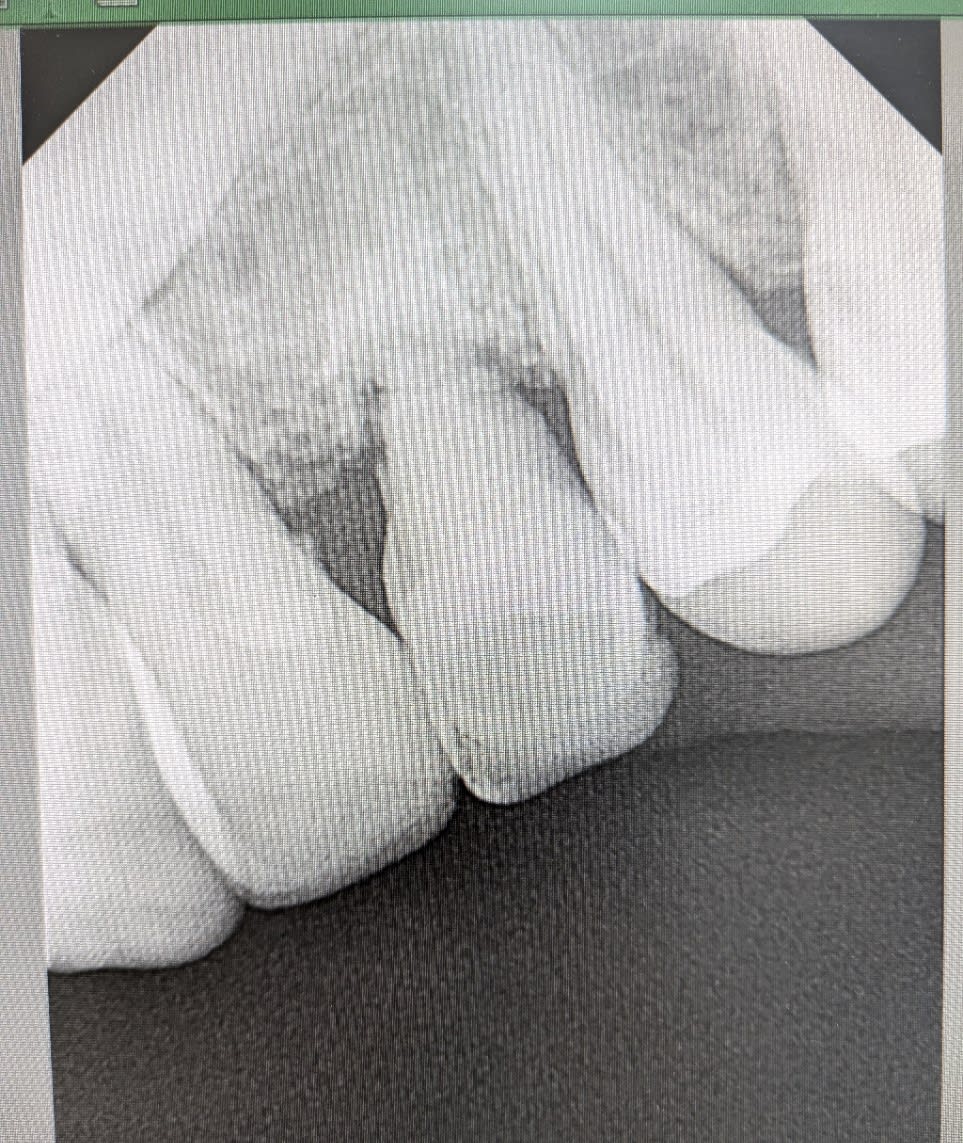

bonjour, je veux bien votre avis sur ce cas :

patiente dont la canine de lait 63 est devenue mobile ( je me demande s il n y a pas une fracture au niveau de la racine) et la canine incluse couchée à 90 degré occupe tout le volume osseux de la corticale externe à la corticale interne sous la 63. l option bridge collé pour remplacer la dent ne me parait pas trop viable dans le temps.

quelqun a déja posé un implant dans une canine incluse? il y a un protocole particulier? je vais forcement toucher le nerf de la canine et je ne vois pas trop comment ça peut aller correctement.

sinon je crains que l extraction de la canine incluse soit extrêmement délabrante et traumatisante même si c est l option qui semble la plus sage.

Image de la canine plus grosse = position palatine à 100%

Elle se situe juste derrière les incisives

La seule difficulté, décoller la muqueuse palatine….

Après quand on voit cette coupe cbct, je ne suis pas certain que l’extraction soit une partie de plaisir.

sur les autres coupes la couronne est en palatin et l apex en vestibulaire, la dent occupe vraiment une grosse partie du volume osseux de de la crête .